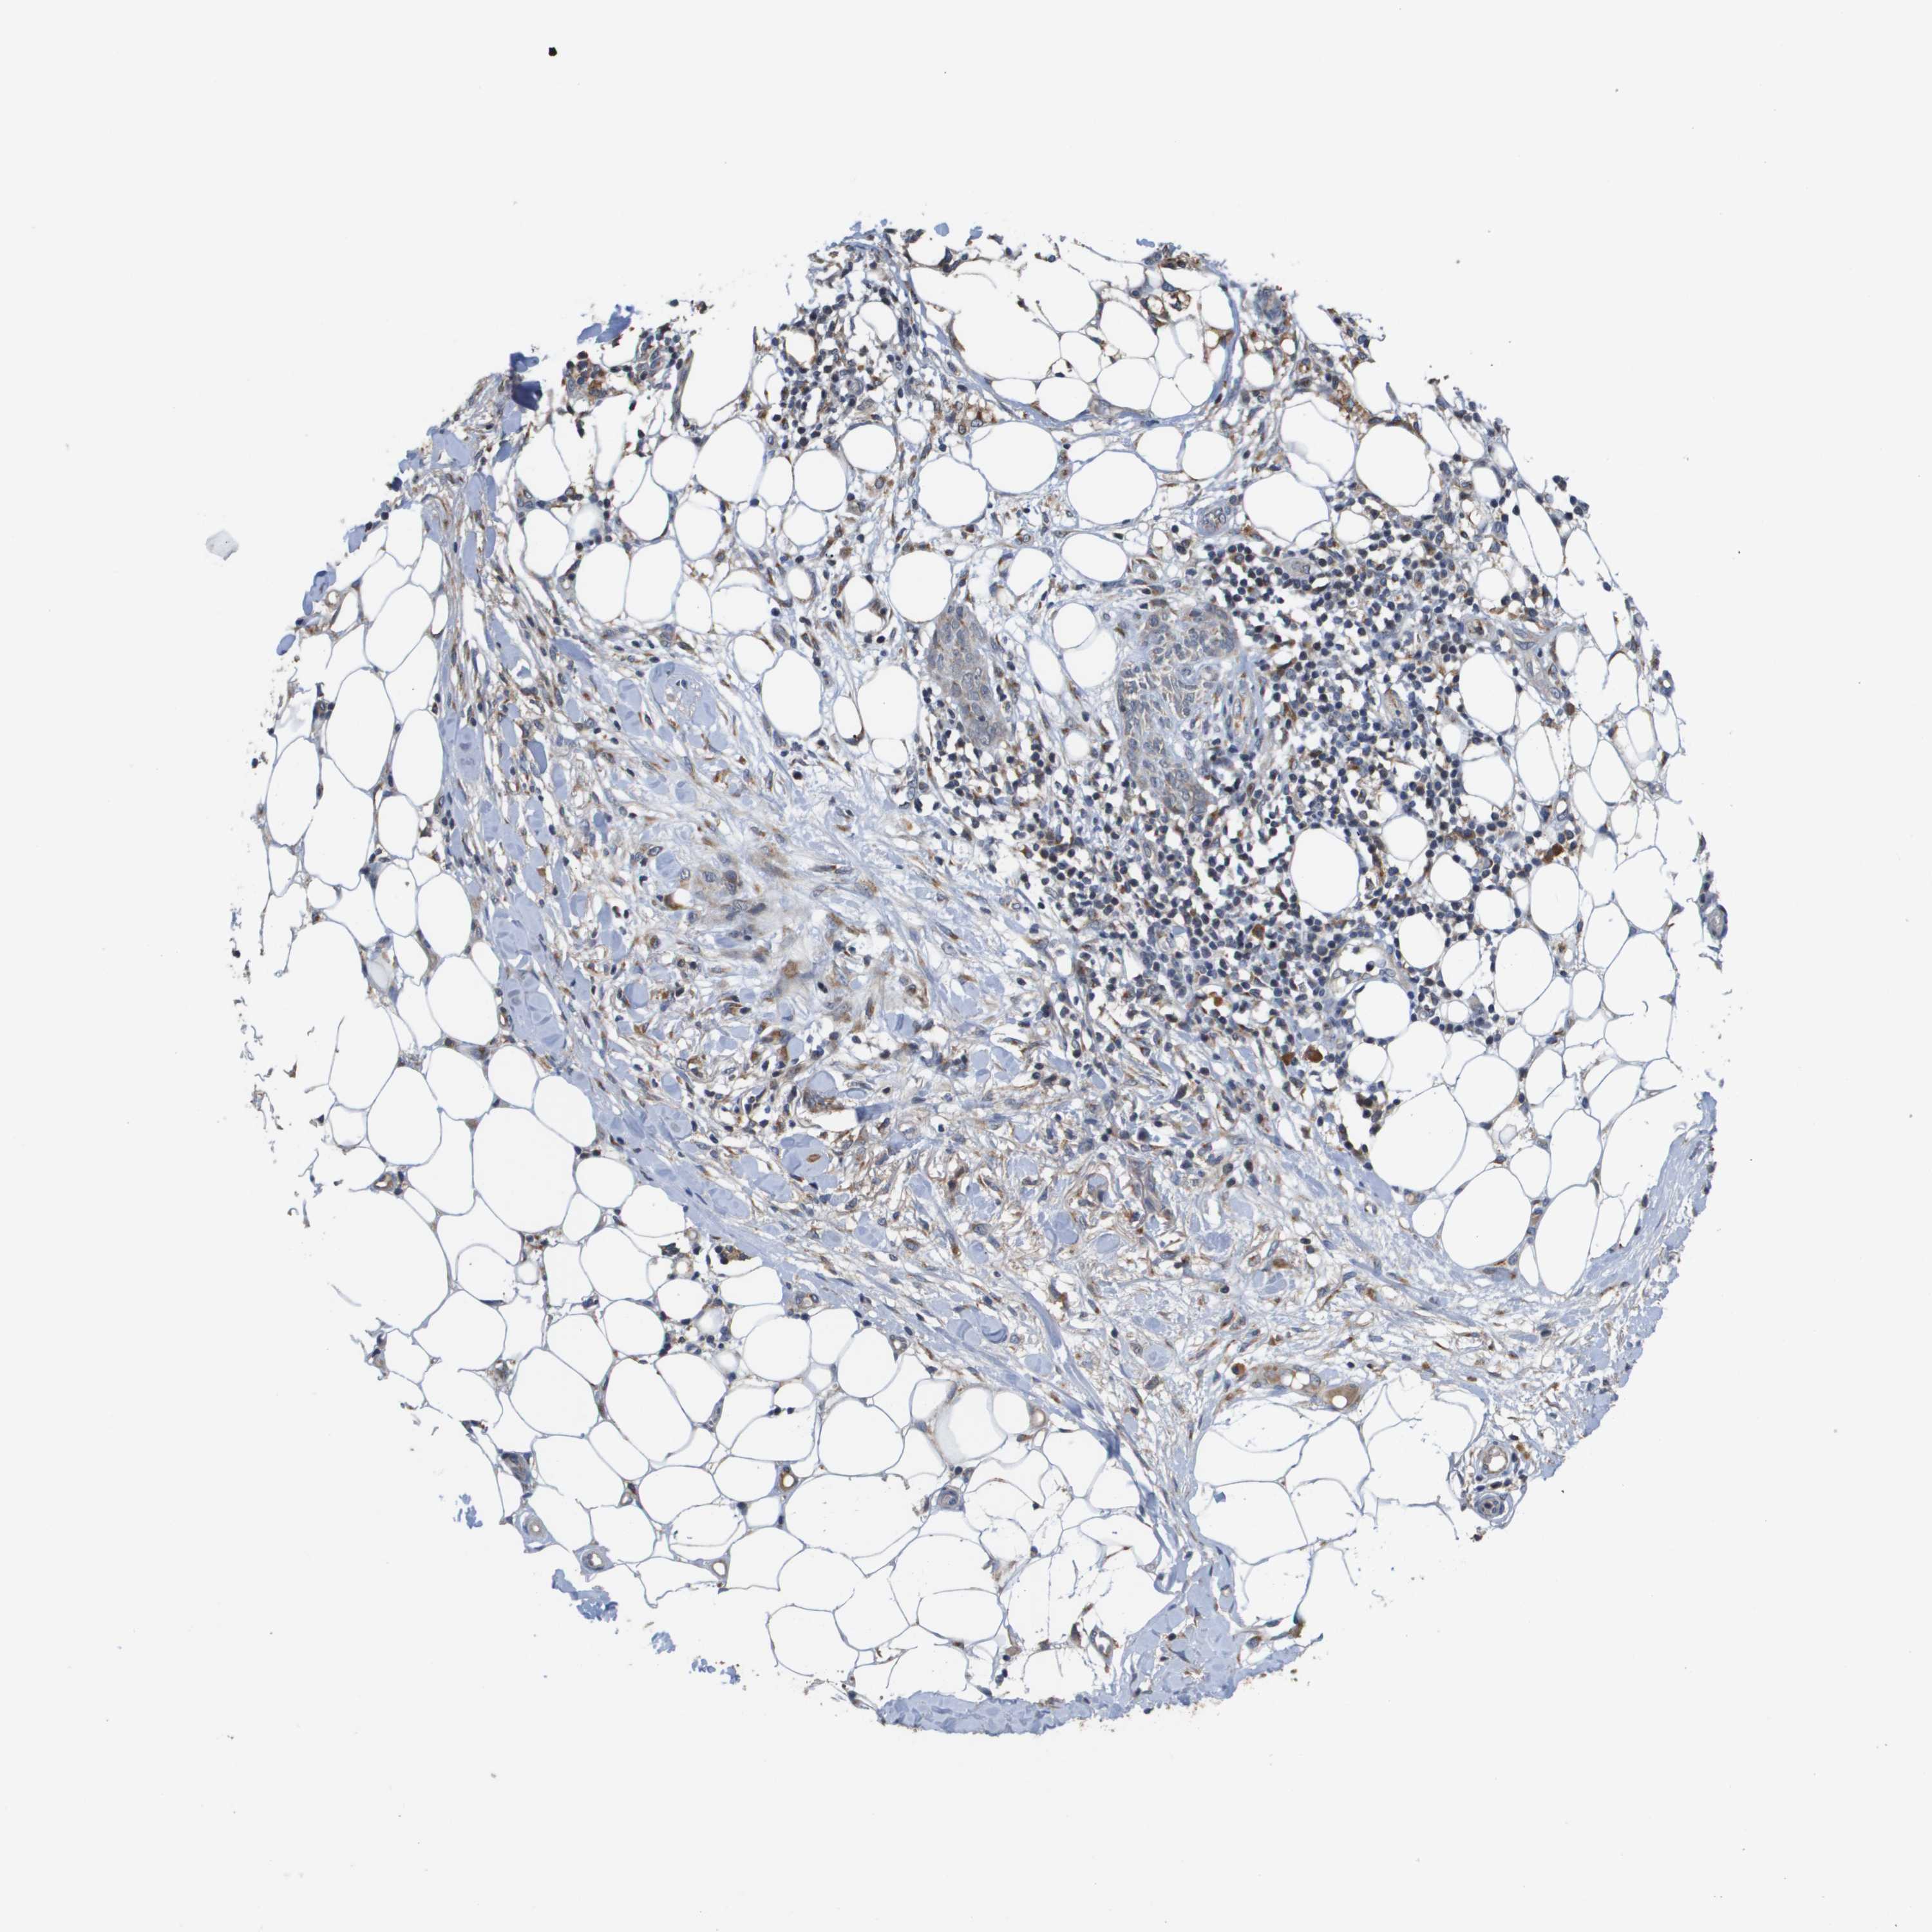

SKIN CANCER - Protein expressioni

A mouse-over function shows sample information and annotation data. Click on an image to view it in a full screen mode. Samples can be filtered based on level of antibody staining by selecting one or several of the following categories: high, medium, low and not detected. The assay and annotation is described here.

Each image is clickable and will lead to virtual microscopy that enables deeper exploration of all samples and also displays staining intensity scores, fraction scores and subcellular localization as well as patient and tissue information for each sample.

Antibody HPA006277

Antibody HPA006507

Antibody CAB017027

Staining

High

Medium

Low

Not detected

Intensity

Strong

Moderate

Weak

Negative

Quantity

>75%

75%-25%

<25%

None

Location

Nuclear

Cytoplasmic/membranous

Cytoplasmic/membranous,nuclear

Basal cell carcinoma